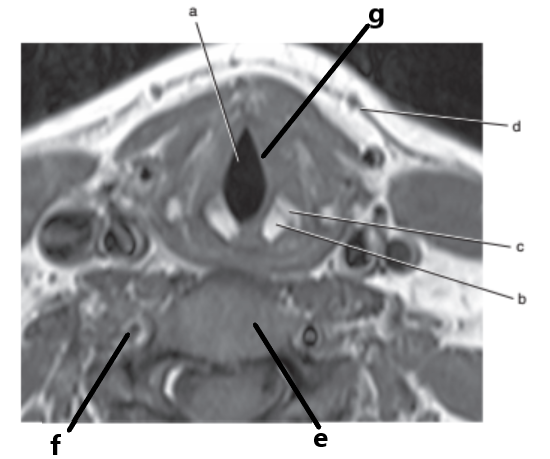

Vocal cords

Larynx

Spinal cord

Glottis